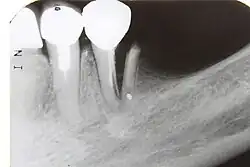

7) Root fracture Mobile or displaced crown segment

Tender tooth that may be bleeding from the gum

Tooth may be discoloured (red or grey)

Fracture line involving the root will be seen as well as the direction If displaced, reposition tooth and check the position with an x-ray

Flexible splint used to stabilise tooth for at least 4 weeks and then reassess tooth stability

Monitor healing for at least 1 year to assess the status of the pulp

Root canal treatment will be needed if pulp necrosis develops (this occurs in ~20% of root fractures)